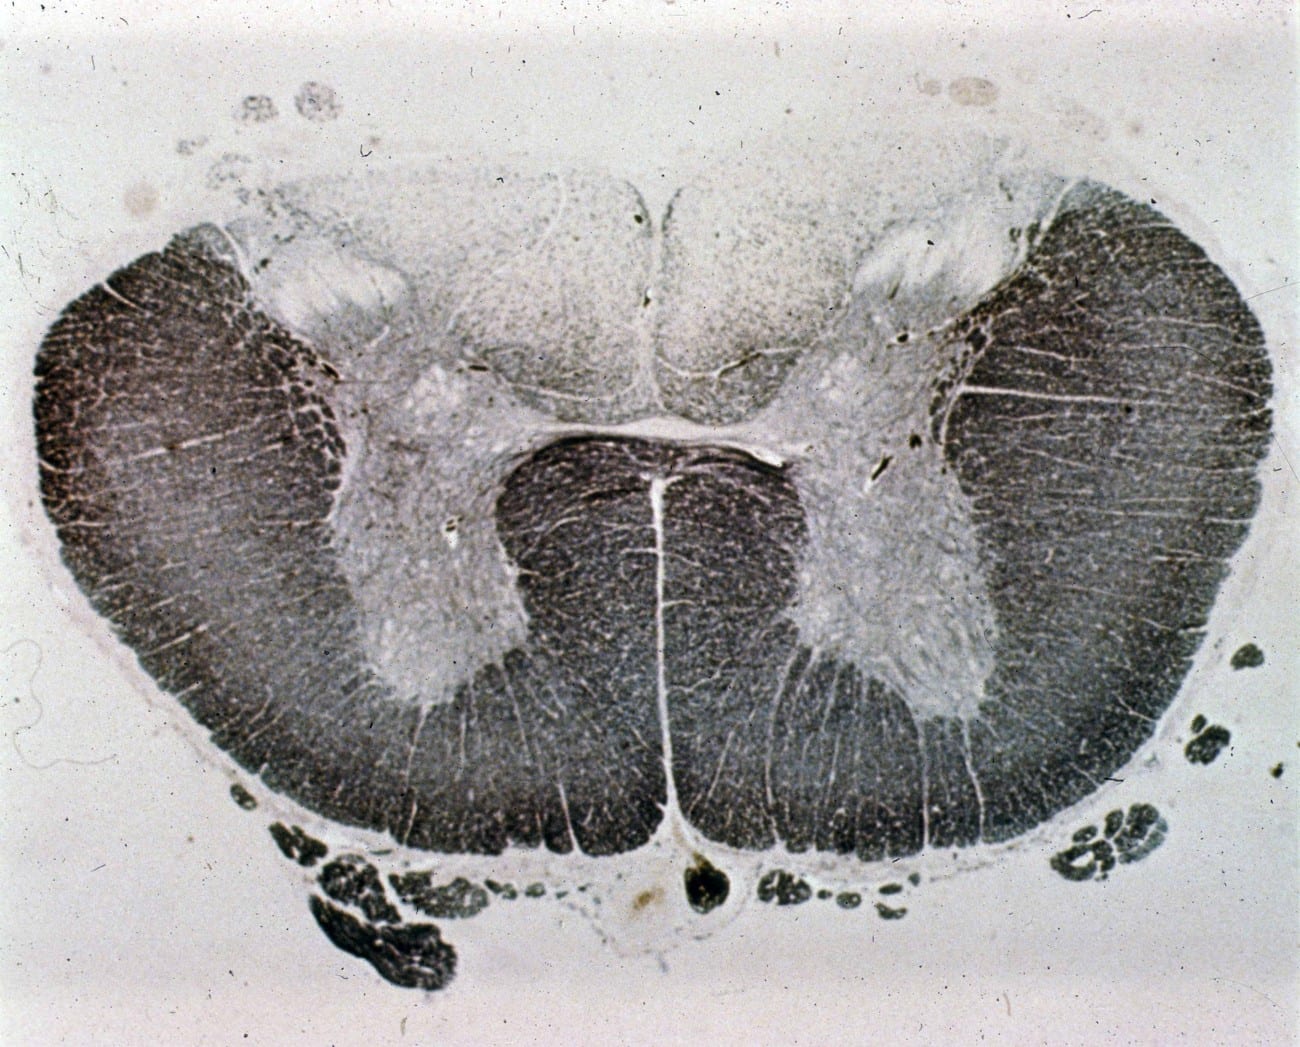

Figure 1 from Tabes Dorsalis in a Patient Presenting With Right Lower Tabes Dorsalis Unilateral tabes dorsalis is a form of tertiary late neurosyphilis in which there is demyelination of the posterior columns of the spinal cord. tabes dorsalis is a slowly progressive degenerative disorder of the dorsal column and dorsal root of the spinal cord. tabes dorsalis is a slow degeneration of the nerve cells and nerve fibers that carry sensory. Tabes Dorsalis Unilateral.

Lumbar Spinal Cord Cross Section Tabes Dorsalis Unilateral tabes is characterized by gait ataxia with romberg’s sign (falling or stepping to one side when standing with. tabes dorsalis is a form of tertiary late neurosyphilis in which there is demyelination of the posterior columns of the spinal cord. tabes dorsalis is a slowly progressive degenerative disorder of the dorsal column and dorsal root of the. Tabes Dorsalis Unilateral.